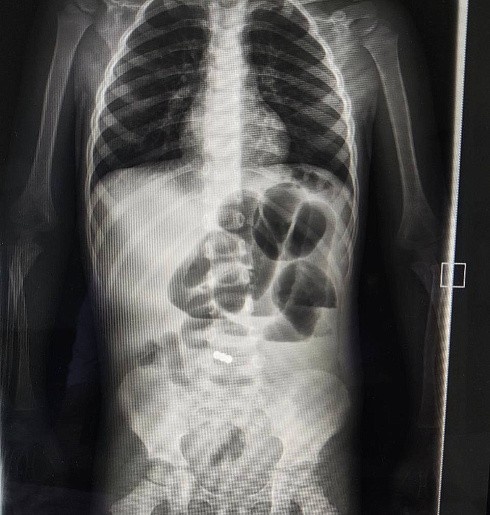

В детскую областную больницу поступил двухлетний ребёнок в крайне тяжёлом состоянии.

У малыша была высокая температура, частая рвота и боли в животе. Врачи выяснили, что в желудочно-кишечном тракте ребёнка находятся магниты. Это самое опасное, что может быть, так как магниты притягиваются друг к другу внутри органов.

«У малыша участок подвздошной кишки с двумя магнитами примагнитился к куполу слепой кишки. Через червеобразный отросток и поврежденную стенку подвздошной кишки магниты были удалены.

Кроме этого во время операции врачи обнаружили врождённую аномалию кишечника – дивертикул Меккеля, который был удален.

Это мешковидное выпячивание тонкой кишки, которое присутствует у некоторых детей с рождения. При воспалении дивертикул Меккеля может послужить причиной его перфорации в свободную брюшную полость с развитием перитонита», – рассказал хирург Якоб Горбачев, который проводил операцию под контролем заведующего детским хирургическим отделением Сергея Савина.